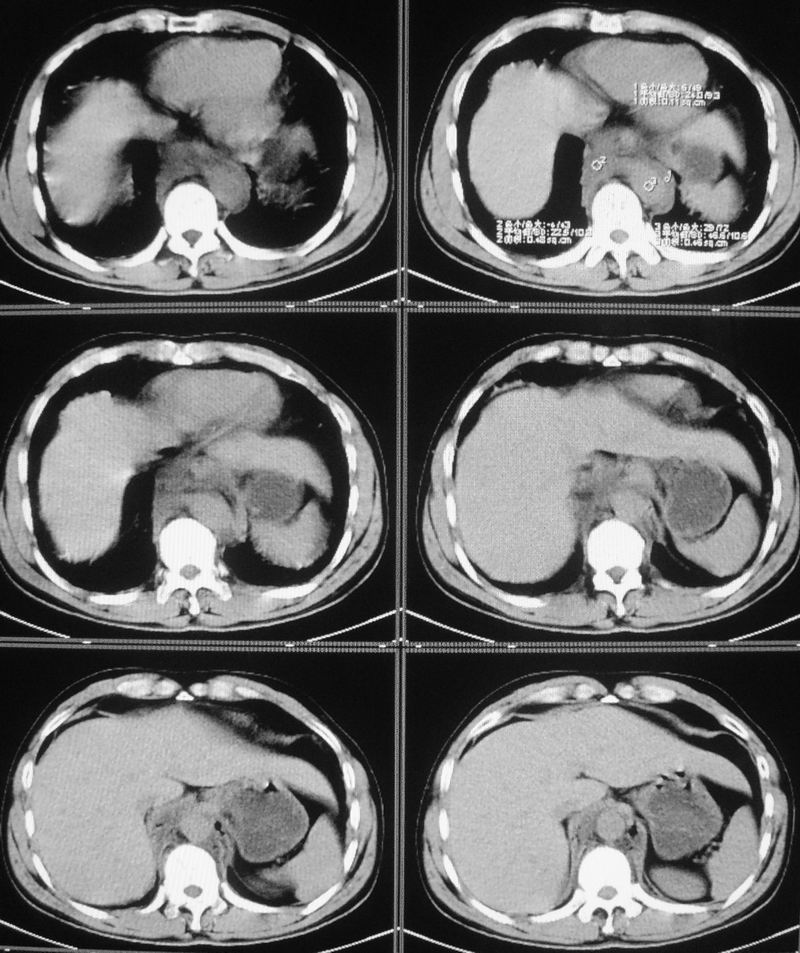

男性,47岁,车祸致胸痛2小时。

请大家看看后纵隔食道及降主动脉周围的软组织密度灶是什么?双侧膈肌脚内侧及椎管内的气体影是怎么回事?

考虑纵隔外伤后积血。

右肺下叶血肿形成。

结合病史多考虑纵隔血肿形成

有外伤病史,两个征象应该认为是外伤所致出血;需再确认是否有骨折,导致的积气。

是后纵隔出血还是出血合并有胸主动脉加层,增强扫描.

结合病史多考虑纵隔血肿形成 ,椎管及右侧腰大肌内侧气体影也与外伤有关。

要不要考虑食道中下段的损伤呢?这样血肿和气体影就都好解释了。